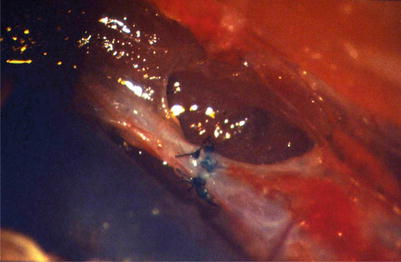

During the whole investigation period, a marked foreign body reaction was seen around the nonabsorbable sutures (Fig. 2.9).

Fig. 2.9

Patent anastomosis of the abdominal thoracic duct, nonabsorbable suture material (Polyamide 6.6.), 8 weeks after surgery, marked foreign body reaction close to the vessel (H-E, tenfold magnification of objective)